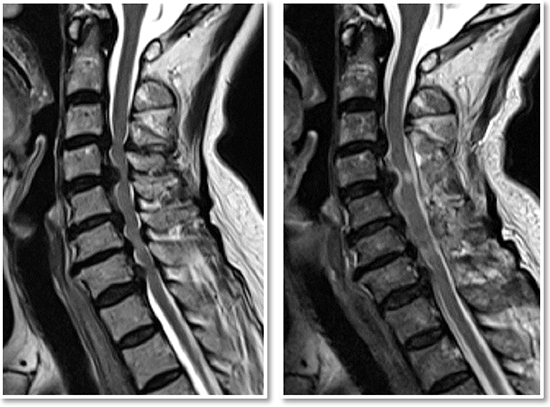

목디스크, 즉 경추디스크는 경추(목의 부분) 영역에서 발생하는 디스크 손상을 의미합니다. 이러한 디스크는 각 척추 사이에 위치하며, 척추의 충격을 흡수하고 유연성을 제공하는 중요한 역할을 합니다.

목디스크는 주로 디스크의 견봉이 손상되거나 내부의 젤이 누출됨으로써 발생합니다. 이런 손상은 디스크의 터짐, 미세한 틈새, 혹은 디스크에 가해지는 과도한 압력 때문에 발생할 수 있습니다

목디스크는 경추와 흉추 부위에서 발생할 수 있으며, 이러한 디스크의 변화는 주로 디스크의 손상된 부분이 주변 신경을 압박하거나 자극함으로써 다양한 증상을 유발합니다.

목디스크는 하중이 한 부위에 집중되어 경추 사이에 있는 추간판이 파열되고 내부의 수핵이 변위될 수 있는 상태를 가리킵니다.

이러한 상태는 공식적으로는 경추 추간판 탈출증으로 알려져 있으며, 목의 추간판이 손상되어 통증과 불편을 초래할 수 있습니다. 목디스크는 일상 활동에서의 부적절한 자세나 무리한 운동, 또는 직업적 요인으로 발생할 수 있습니다.